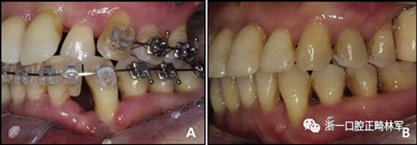

圖13.下頜左側(cè)尖牙近中缺損的改變:A,治療中;B,治療后

治療后頭影測量分析顯示上頜切牙的傾斜和唇部相對于E線的位置都得到改善(表II)。治療前后頭影測量圖的疊加顯示上頜和下頜切牙的向后移動伴隨著上頜切牙的推入。垂直維度在跨學(xué)科正畸綜合治療后被保持。三維模型的疊加顯示了上頜牙列的遠中移動,下頜前牙的回縮和上頜右側(cè)尖牙的推入(圖14)。

圖14.頭影測量和3維模型的疊加